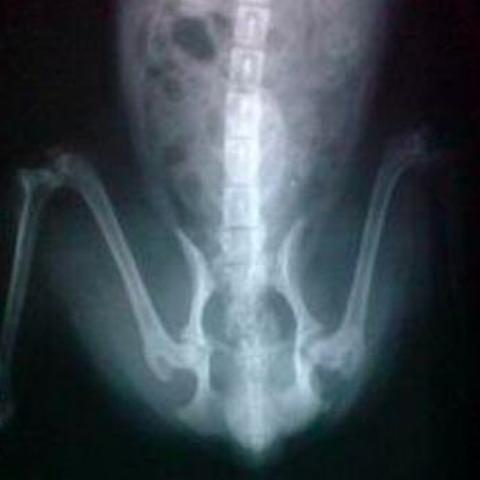

一.髋关节发育不全症(CHD)

CHD的临床症状一般在4~12月龄间出现,但也有少数犬会在12~36月龄间出现。有些犬存在CHD但是短期内却不表现任何症状。CHD的临床症状变化范围很大,从非常轻微的不适到严重的跛行共分为七级。主要表现为:

1)喜卧、不愿运动;特别不愿上下楼梯; 2)躺下后起立费劲;3)奔跑时呈现三脚跳

此病虽然有遗传所致,但后天影响因素也极为重要。例如,幼犬的饮食中钙质过多,生长发育太快导致的骨骼负担过重,成长期由于过度运动等原因造成的髋关节受损等等,都会加重遗传因素所致的病情。

CHD一旦发作,一切药物都不能根治。只能手术。目前的手术方法主要有:趾骨肌切断术,趾骨联合切除术,骨盆三刀切手术,股骨头切除关节成形术,全髋关节置换术等等。

最好的办法是防患于未然。尤其在金毛4-9个月的快速生长期内,要注意其运动安全和饮食营养控制。